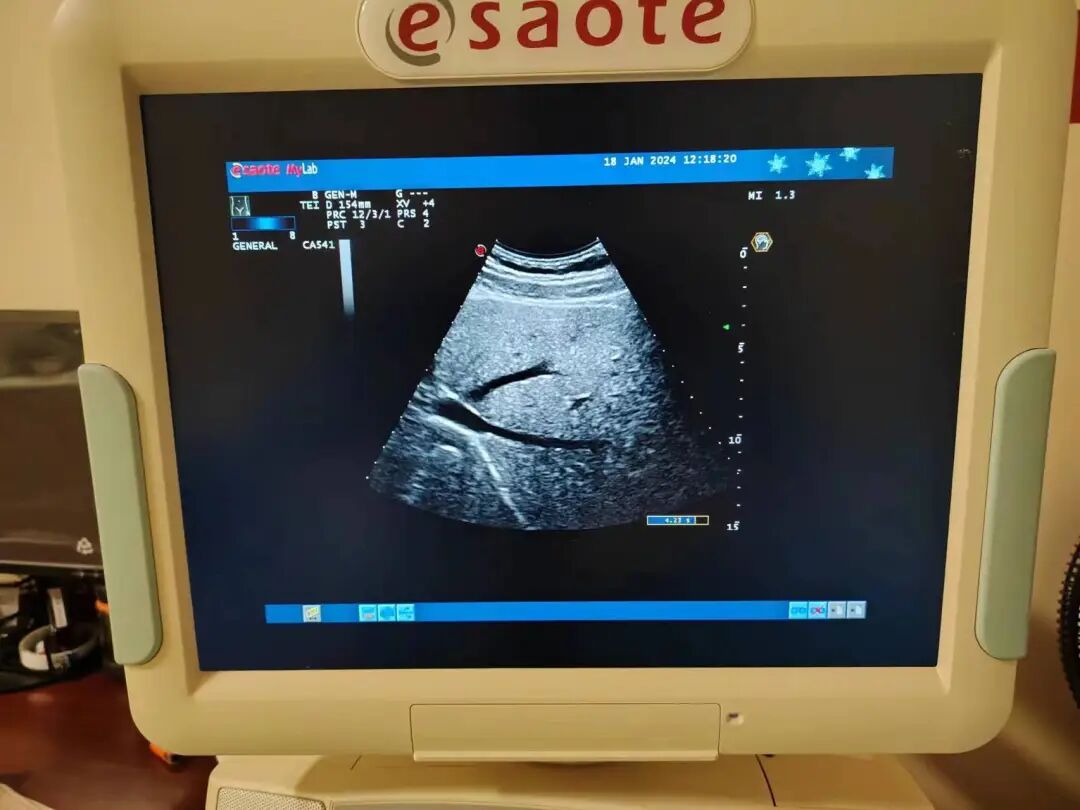

4.故障处理

更换声头晶体,更换前壳,重装完毕后上机测试,探头正常使用。

5.维修后效果